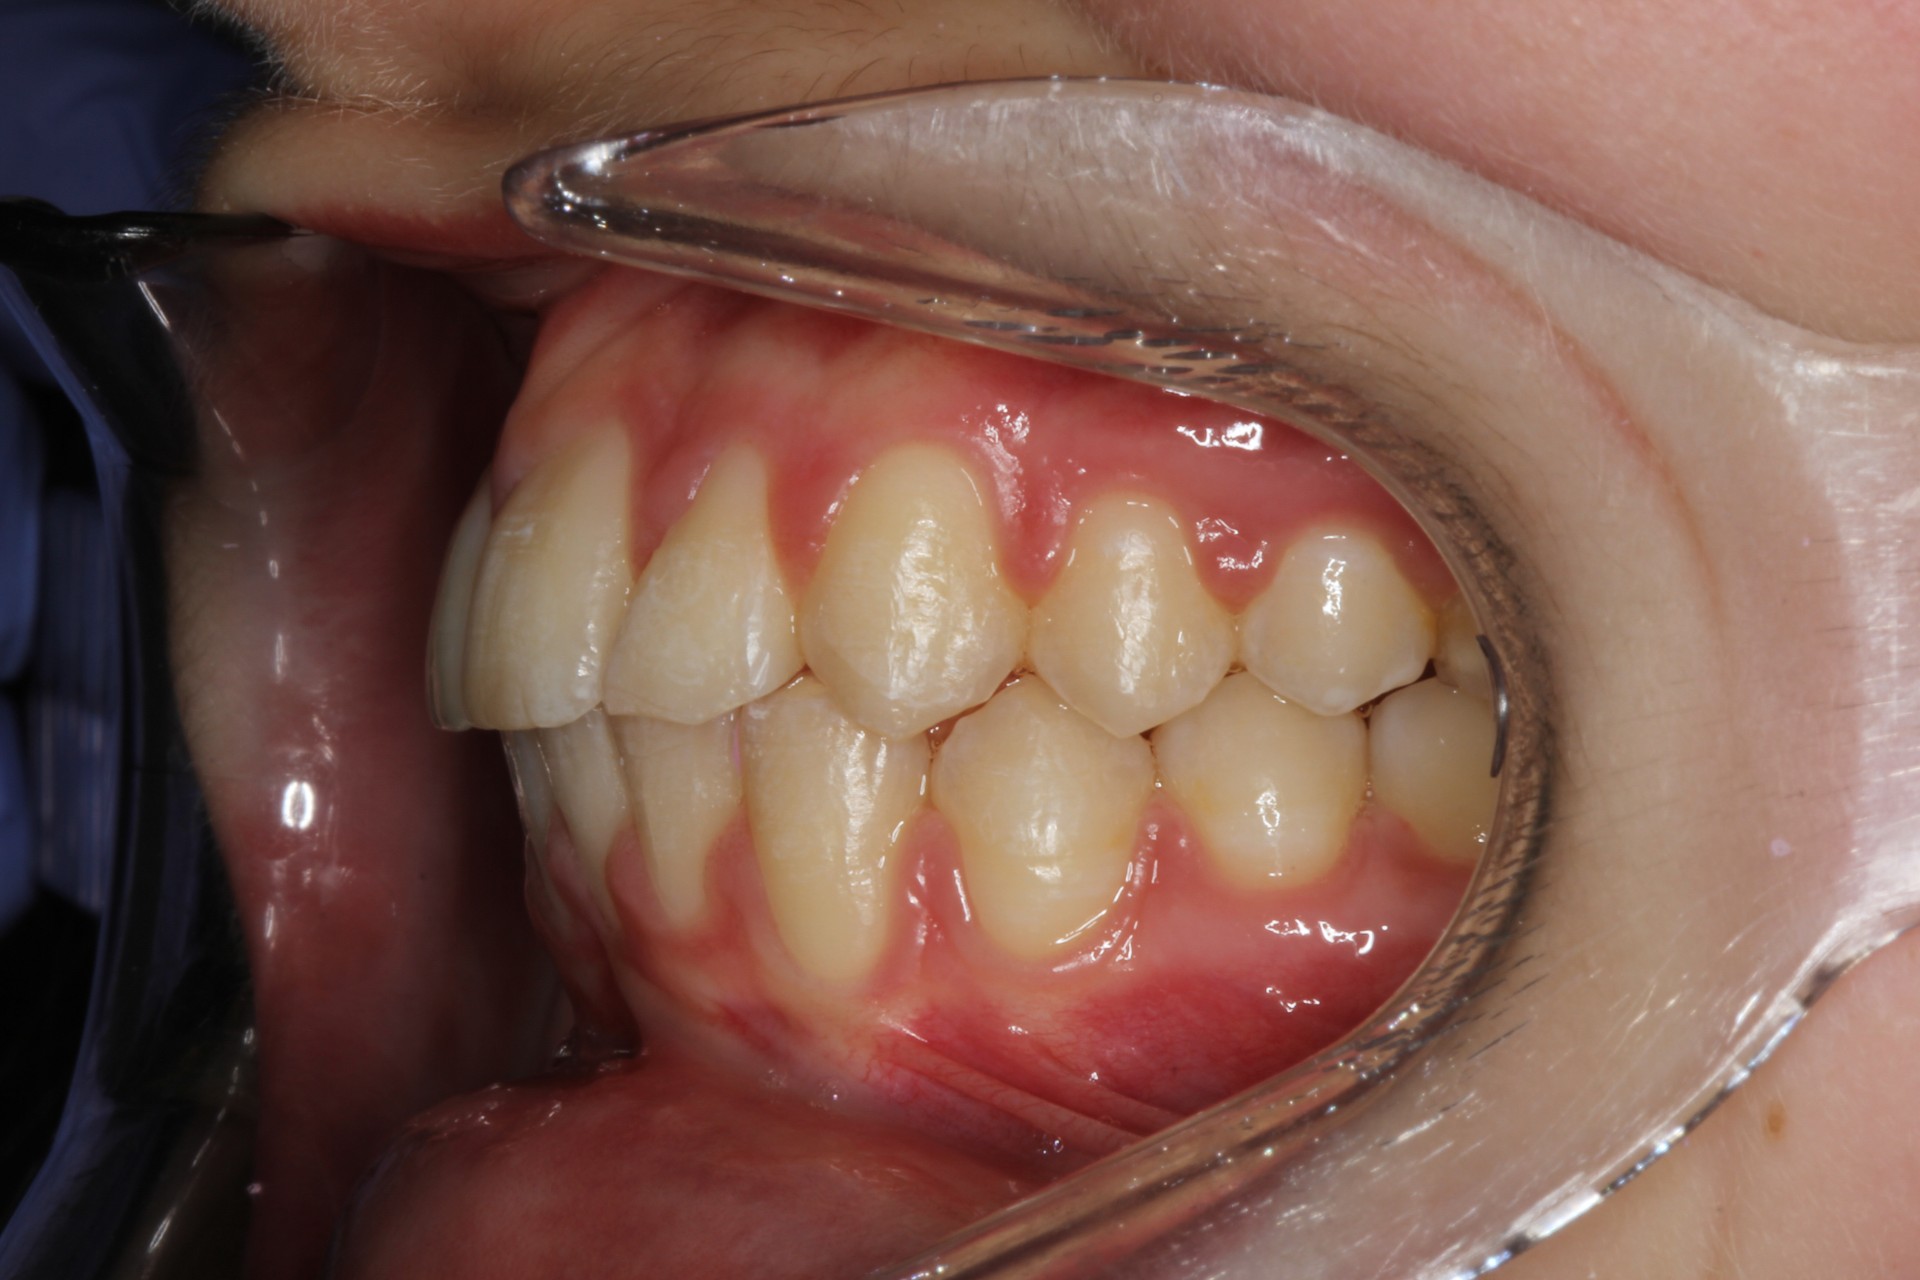

Protruding front teeth – Child case